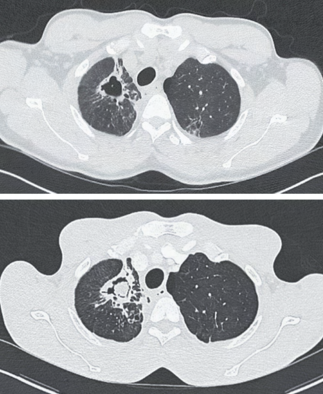

Recent studies indicate that Generative Pre-trained Transformer 4 with Vision (GPT-4V) outperforms human physicians in medical challenge tasks. However, these evaluations primarily focused on the accuracy of multi-choice questions alone. Our study extends the current scope by conducting a comprehensive analysis of GPT-4V's rationales of image comprehension, recall of medical knowledge, and step-by-step multimodal reasoning when solving New England Journal of Medicine (NEJM) Image Challenges - an imaging quiz designed to test the knowledge and diagnostic capabilities of medical professionals. Evaluation results confirmed that GPT-4V outperforms human physicians regarding multi-choice accuracy (88.0% vs. 77.0%, p=0.034). GPT-4V also performs well in cases where physicians incorrectly answer, with over 80% accuracy. However, we discovered that GPT-4V frequently presents flawed rationales in cases where it makes the correct final choices (27.3%), most prominent in image comprehension (21.6%). Regardless of GPT-4V's high accuracy in multi-choice questions, our findings emphasize the necessity for further in-depth evaluations of its rationales before integrating such models into clinical workflows.